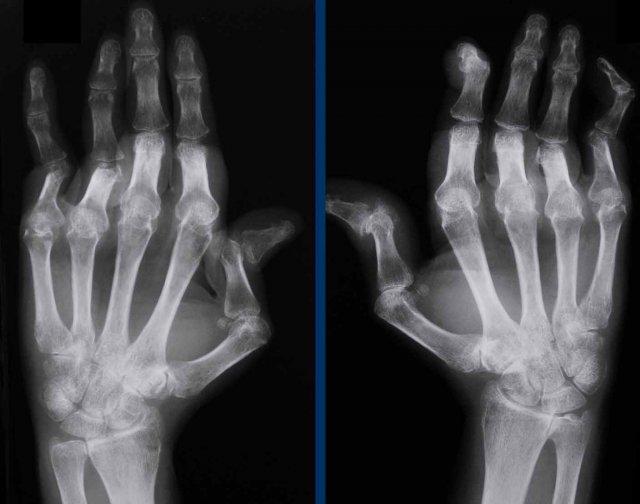

Ngón cái chữ Z và ngón tay cổ thiên nga ở bệnh nhân SLE.

Các biến dạng này được cho là hậu quả của tình trạng viêm mức độ thấp ở màng hoạt dịch và bao khớp, dẫn đến lỏng lẻo dây chằng và co rút cơ.

Biến dạng cổ thiên nga

Đây là một ví dụ khác với biến dạng trục khớp lan rộng mà không có bào mòn hay dấu hiệu tổn thương sụn khớp ở bệnh nhân SLE.

Một bệnh nhân khác với biến dạng cổ thiên nga.

Thông thường, biến dạng này có thể hồi phục ở giai đoạn sớm của bệnh.

Hoại tử vô mạch

Hoại tử vô mạch là biến chứng thường gặp trong SLE, xảy ra ở tới 15% bệnh nhân.

Chỏm xương đùi và mâm chày là các vị trí hay gặp nhất, tuy nhiên các vị trí khác cũng có thể bị ảnh hưởng.

Bệnh nhân SLE có đau xương cần được nghi ngờ hoại tử vô mạch.

Hoại tử vô mạch trong SLE có thể xảy ra ngay cả khi không sử dụng corticosteroid.

Hình ảnh

Tăng tỷ trọng ở đầu xa xương đùi theo dạng hình vòng hoa, biểu hiện của hoại tử vô mạch ở bệnh nhân SLE.

A. Bán trật khớp bàn ngón tay (MCP) thứ 1 mà không có bào mòn ở bệnh nhân SLE. Đây không phải là hình ảnh điển hình của SLE và có thể gặp trong các thể viêm khớp khác như thoái hóa khớp chẳng hạn.

B. SLE ở khớp vai. Xẹp chỏm xương cánh tay kèm một số mảnh xương rời do hoại tử vô mạch. Cả liệu pháp corticosteroid lẫn bản thân bệnh SLE đều liên quan đến nguy cơ hoại tử vô mạch gia tăng.